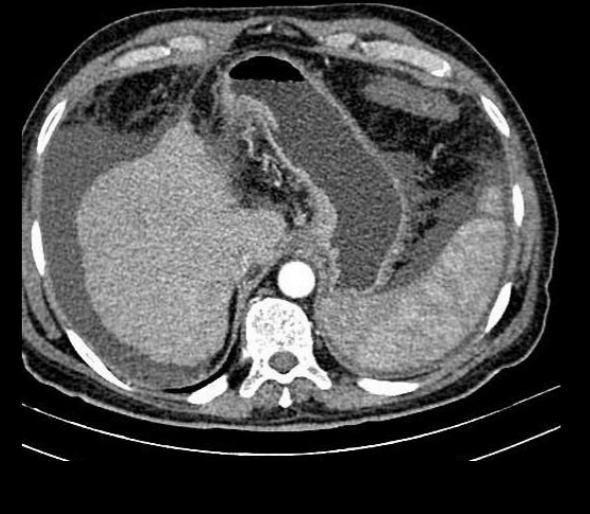

y en tm como se ve?

A

Hígado hipodenso

Bazo mas hiperdenso

Hígado graso